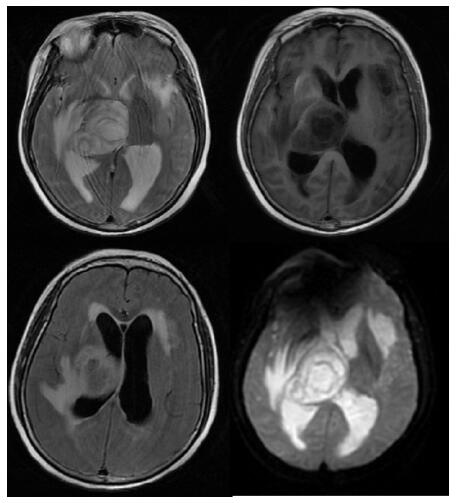

患者,女,54岁,工人,因“头晕5 d”于2019年9月29日至浙江大学附属第二医院急诊就诊。5 d前患者无明显诱因出现头晕,伴行走不稳、四肢乏力,无发热、咳嗽咳痰、胸闷气促、恶心呕吐、四肢抽搐等,未就诊。我院急诊头颅磁共振(MRI)示:右侧丘脑及左侧岛叶异常信号,局部累及右侧中脑(图 1),考虑脑多发占位性疾病。在急诊抢救室予甘露醇100 mL静滴脱水降颅压等对症治疗,5 h后患者逐渐意识模糊。急查血常规:白细胞16.1×109/L,中性粒细胞百分比73.4%;头颅CT示右侧丘脑、左侧岛叶病变,伴脑室扩张(图 2);急诊行“双侧脑室外引流术”,术中引流液呈淡血性。术后诊断:⑴(右侧丘脑)颅内占位性病变,脓肿首先考虑,肿瘤需排除;⑵脑积水;⑶脑疝。患者带气管插管转入ICU进一步治疗。当时体温38.3℃,脉搏99次/min,呼吸频率24次/min,血压169/87 mmHg(1 mmHg= 0.133 kPa),颈软,神志昏迷,右侧瞳孔3 mm,左侧瞳孔2.5 mm,对光反射迟钝。双肺呼吸音粗,可闻及少量啰音。左侧病理征阳性。患者3个月前曾因“反复胸闷气促伴发热1个月余”在本院风湿科住院,当时胸部高分辨CT示两肺间质性肺炎、下叶为著(图 3);血化验示血沉偏高,抗心磷脂抗体阳性;诊断为“间质性肺炎”,住院期间予甲泼尼龙40 mg/d静滴×8 d,60 mg/d静滴×6 d,共住院14 d;出院后予口服甲泼尼龙40 mg/d联合雷公藤多苷片每次20 mg,一日2次治疗;此后规范于本院门诊复诊。本次起病前2个月甲泼尼龙已减量至36 mg/d口服治疗。

| A:两肺间质性肺炎,下叶为著(2019-06-23);B:(2019-09-30)两肺间质性肺炎,下叶为著,较前(2019-06-23)部分好转 图 3 患者胸部HRCT结果 |

转入ICU后呼吸机辅助通气、甘露醇100 mL/8 h静滴脱水、头孢呋辛1.5 g/12 h静滴抗感染,肠内营养等支持治疗。当晚血常规:白细胞13.3×109/L,中性粒细胞百分比85.3%,C反应蛋白17.1 mg/L,降钙素原0.64 ng/mL。脑室外引流术后次日血化验:白细胞16.6×109/L,中性粒细胞百分比92.8%,C反应蛋白78.4 mg/L;从脑室外引流管留取脑脊液检验:有核细胞6×106/L,红细胞1 960×106/L,蛋白含量1.717 g/L,葡萄糖4.72 mmol/L,细菌培养阴性,涂片未找到细菌;复查头颅CT示:脑室扩张好转,右侧丘脑、左侧岛叶病变伴出血(图 2);胸部CT示,两肺间质性肺炎下叶为著,较前(2019年6月21日)部分好转(图 3)。考虑到炎症指标升高,遂改哌拉西林他唑巴坦3.375 g/12 h静滴抗感染。此后经脑室外引流管反复留取脑脊液送检涂片及培养均阴性。术后第5天行“导航下立体定向颅内病灶活检术+双侧omaya囊置入术”,术中穿刺液呈黄色黏稠脓性,考虑脑脓肿,留取脓液送高通量测序(next-generation sequencing, NGS),并升级为美罗培南2 g/8 h联合利奈唑胺0.6 g/12 h静滴抗感染治疗。术后第7天患者突发血压升高、瞳孔不等大,昏迷程度加深;急查头颅CT示,双侧脑室钻孔引流术后改变,双侧侧脑室引流管走形区出血伴血肿形成;右侧丘脑区积液、积血,双侧脑室积血新发(图 4),甘露醇加量至250 mL/8 h联合地塞米松5 mg/6 h静滴加强脱水;当日术中脓液高通量测序结果回报:皮疽诺卡菌(序列数52 867个)、支气管戈登菌(序列数10个)。确诊脑诺卡菌病,抗菌治疗方案改为亚胺培南西司他丁0.5 g/6 h静滴,联合利奈唑胺0.6 g/12 h和复方磺胺甲恶唑片(0.48 g/片)3片/6 h口服。此后患者仍伴低热,炎症指标呈上升趋势。术后2周患者再次突发血压升高、瞳孔不等大、对光反射消失、神志深昏迷,急查头颅CT示再发脑疝(图 5),急诊行“去骨瓣减压术+脑内血肿清除术”,术后患者仍呈深昏迷状态,双侧瞳孔散大、对光反射消失,次日自动出院。